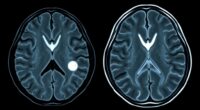

How do clinics make certain of accurate diagnoses and effective treatment plans? They leverage advanced diagnostic tools and technologies. Imaging advancements, like high-resolution MRI and CT scans, provide detailed visuals of inner ear structures, helping pinpoint issues with precision. These imaging techniques allow specialists to visualize anomalies that might be missed with traditional exams. Additionally, data integration plays an indispensable role, combining test results, patient history, and imaging data into a comprehensive view. This seamless integration enables clinicians to identify patterns quickly, reducing diagnostic errors. Modern clinics also use specialized audiometric tools and electrophysiological testing to assess hearing function thoroughly. Comprehensive assessment is essential for capturing the full scope of complex hearing issues. Together, these technologies streamline the diagnostic process, ensuring you receive targeted, effective treatment based on accurate, holistic insights into your hearing health.